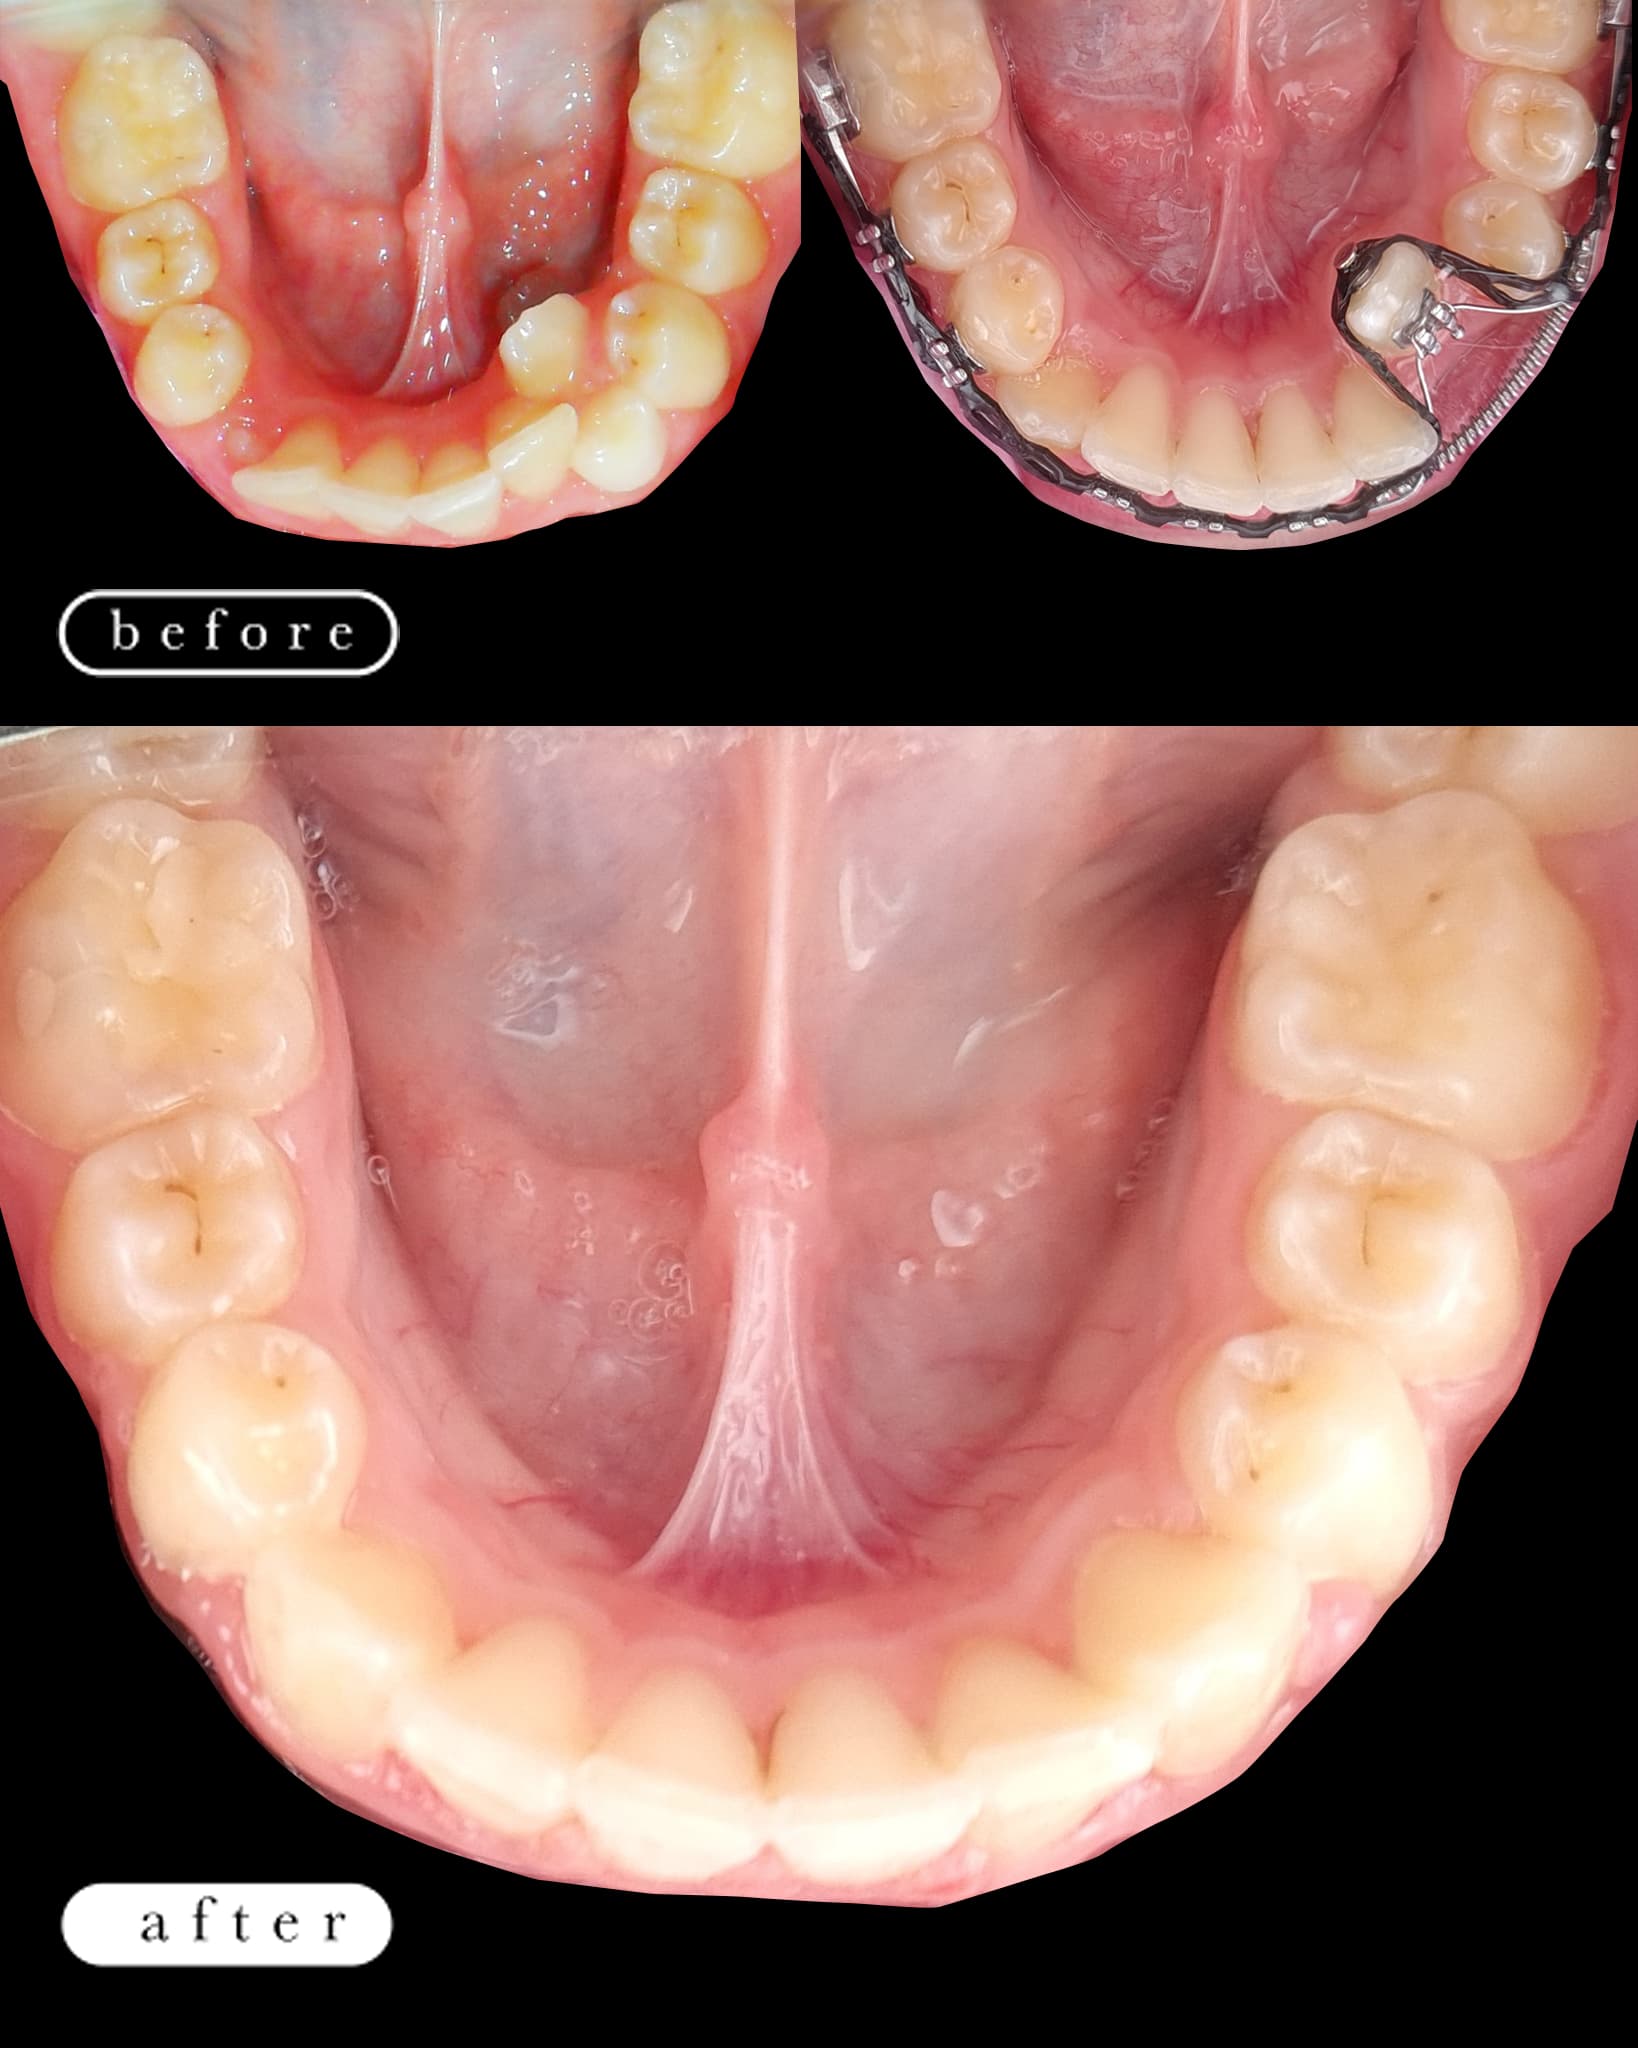

O našoj kvaliteti najbolje govore naši rezultati!